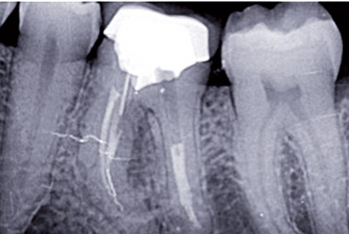

Article réservé à nos abonnés Dépistage des foyers infectieux bucco-dentaires

La cavité buccale est un milieu particulièrement septique. Elle est le siège de multiples infections aiguës ou chroniques dentaires et/ou...